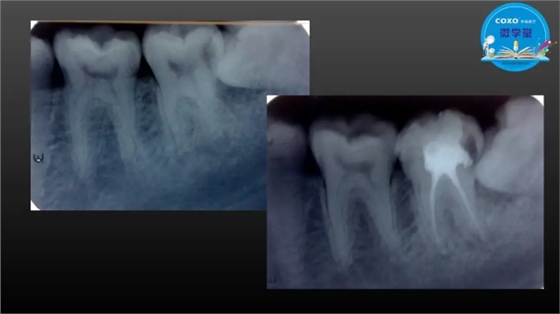

主任医师,牙体牙髓副主任, 广东省口腔医院牙体牙髓科 主任医师。2003年硕士研究生毕业,研究方向为牙体牙髓病学,擅长于牙体牙髓病的诊断、龋齿、牙髓炎、根尖周病的治疗以及前牙美容修复。